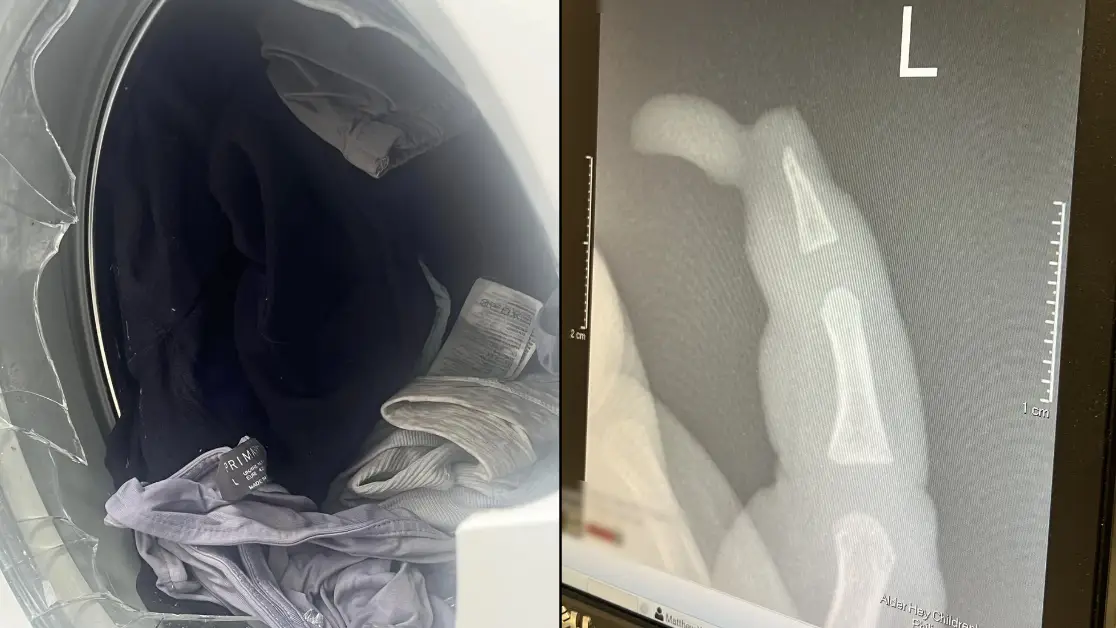

She had to rush her son to hospital for an operation

The terrifying incident occurred after a match on Saturday (12 October)